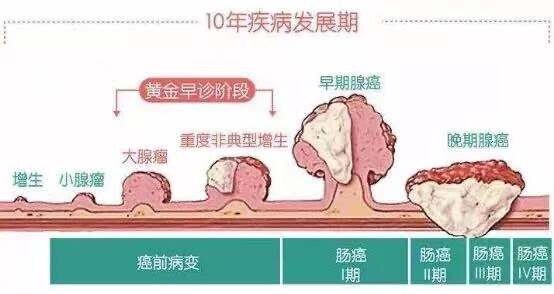

结肠癌是常见的发生于结肠部位的消化道恶性肿瘤,以40-50岁年龄组发病率最高,男女比例为2-3:1,发病率占胃肠道肿瘤的第3位。超过80%的结肠癌是由结肠息肉演变而来,肠道息肉是在大肠粘膜表面的新生物,有一定的癌变发生率,一般要经历从正常粘膜 ——炎性增生——增生性息肉——腺瘤性息肉—— 癌变的过程,从增生性息肉到肿瘤发生一般需要5-10年的时间。

多数大肠腺瘤性息肉起病隐匿,无任何临床症状,少数表现为大便习惯改变、腹泻稀便、次数增多,也有部分以便秘为主,息肉长大后可出现大便带血和粘液。结肠癌患者往往有腹痛、便血、消瘦、贫血等全身症状,有些没有明显肠道表现,容易漏诊,需要进行肠镜检查,如果等到有明显症状再来就诊时,往往病情已较为复杂。

因此,超过3个月以上的腹泻、便秘、腹部不适患者需要进行肠镜检查,尤其是有家族史的人更应该提高警惕,定期进行肠道检查,一旦发现有肠息肉,应尽可能将其切除。